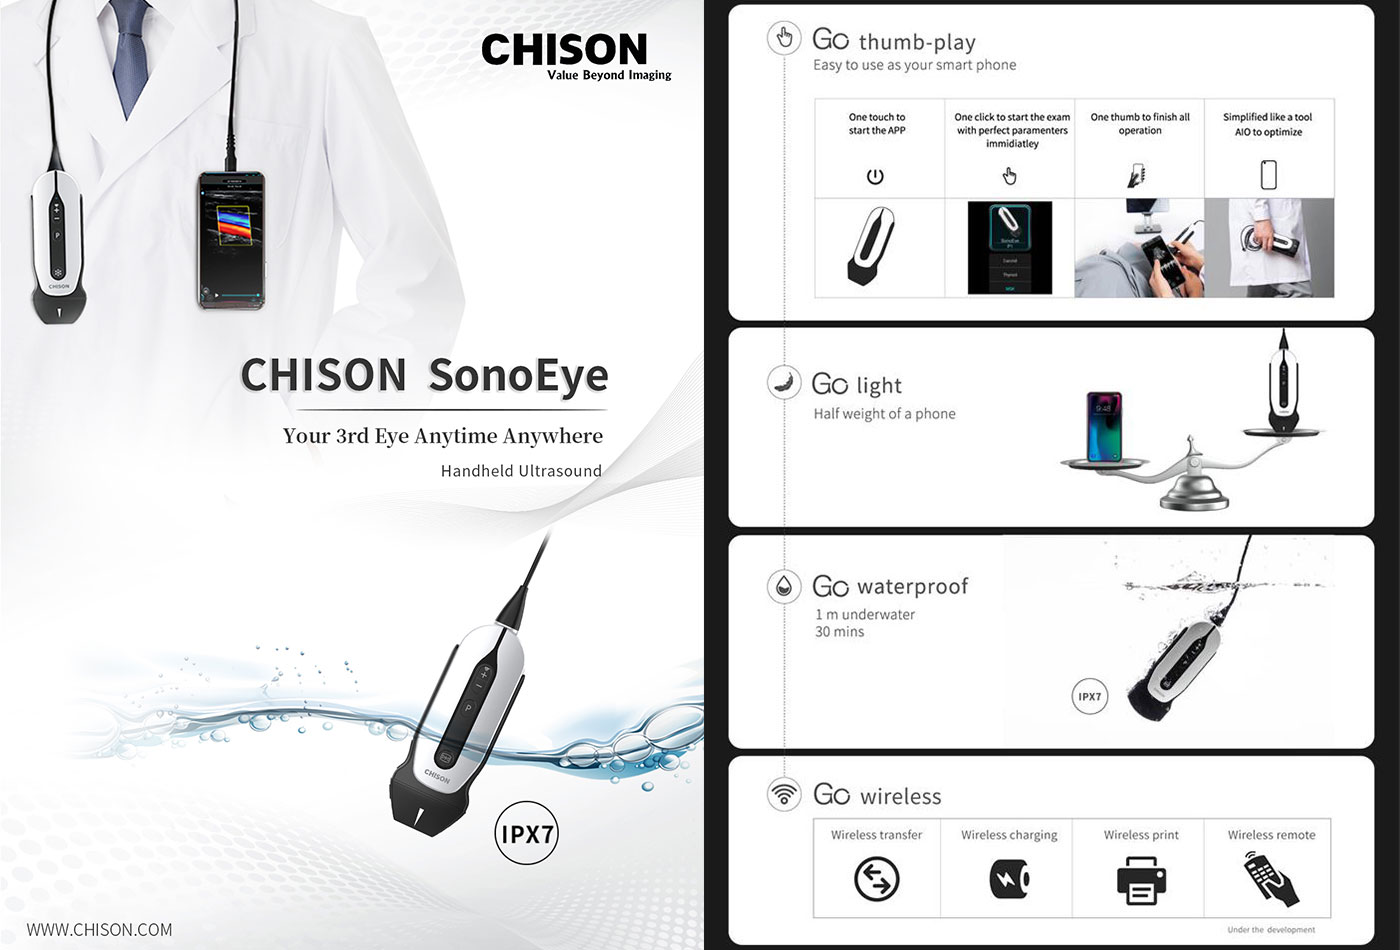

CHISON SonoEye

CHISON SonoEye can help to provide high quality patient care in any location. Featuring an adaptable design that goes from pad to mobile phone, increasing the portability, and making it possible to work together with doctors from patient to patient all the time, initially in point of care applications and longer terms in primary care.

Go Light Half weight of a phone, highly integrated design, less volume.

Go Light Half weight of a phone, highly integrated design, less volume.

SonoEye provides a flexible connection with smart phone or pad.

Go Waterproof

Go Waterproof

SonoEye, a hand-held ultrasound, gives you the power to sterilize and clean freely. (Meet the IPX67 standard)

Go thumb-play

Go thumb-play

? One touch to start an ultrasound exam.

? One thumb to finish all operation.

? Simplified workflow assures you to use it as easy as your smart phone.